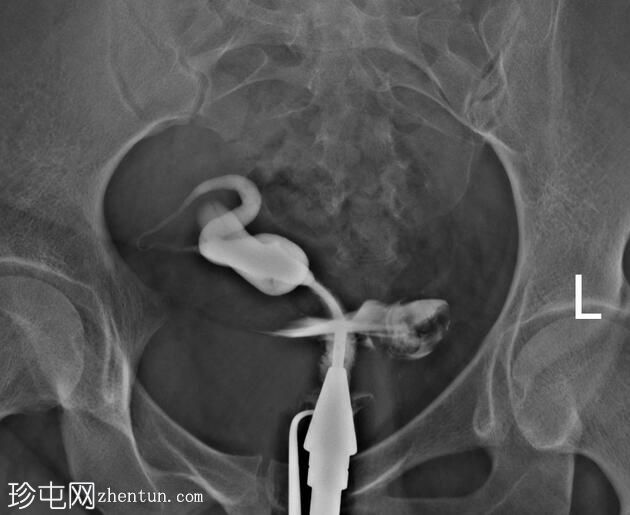

子宫体位于盆腔右侧旁中线,形态及轮廓正常。

宫颈管长度及黏膜表面正常,扩张正常。

右侧输卵管充盈,呈逐渐扩张,内有造影剂残留,无因输卵管积水导致的造影剂溢出。

左侧输卵管出现腹膜溢出。

输卵管积水是指输卵管内充满液体的扩张。